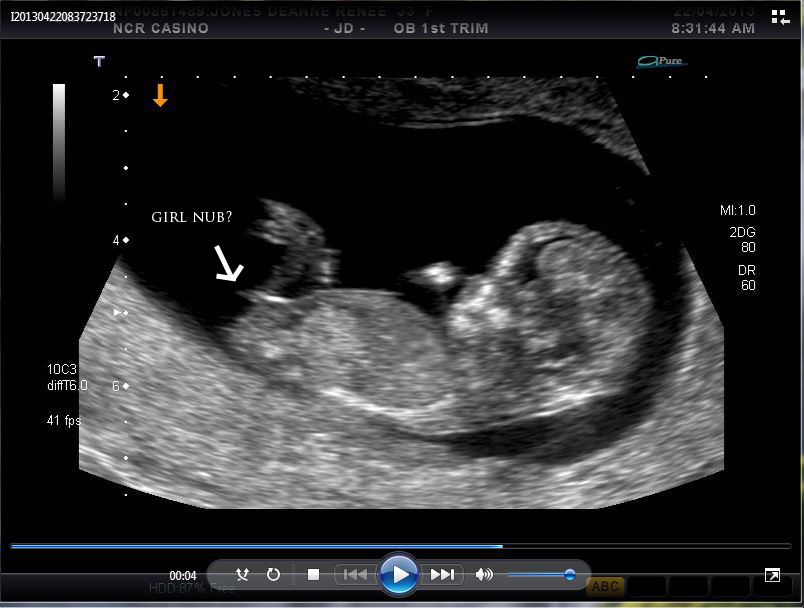

Tech said Girl, just wondering if others agree. Or if there is any chance it could turn boy... was secretly hoping for a boy, to give us two girls two boys!

12 weeks and 3 days, much thanks in advance :)

Looks girly to me

Anything could happen, but looks girly

Yes it does look girly.....but nubs aren't 100% :)

There's a small chance it may still angle up but I'd plan for pink.

I'm thinking girl

Looks pretty girly. But, of course, nothing is written in stone with nubs.

thanks for the replies.. everyone has said girl so far.. oh well, girls are awesome too :)

I would too say girl. Sorry

I think girl!